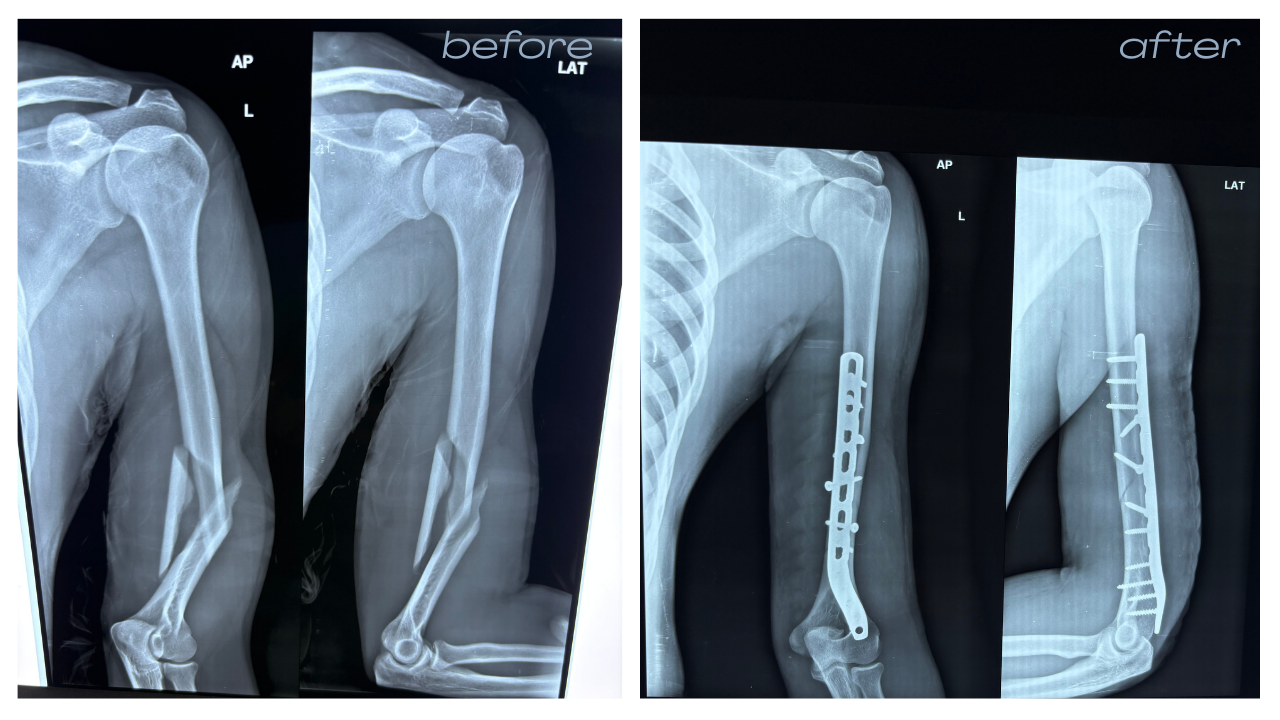

Orthopedic Trauma and Fracture Fixation

Expert management of complex fractures and accidental injuries with a focus on rapid recovery. We provide 24/7 emergency stabilization followed by advanced fixation or non-surgical bracing as required.